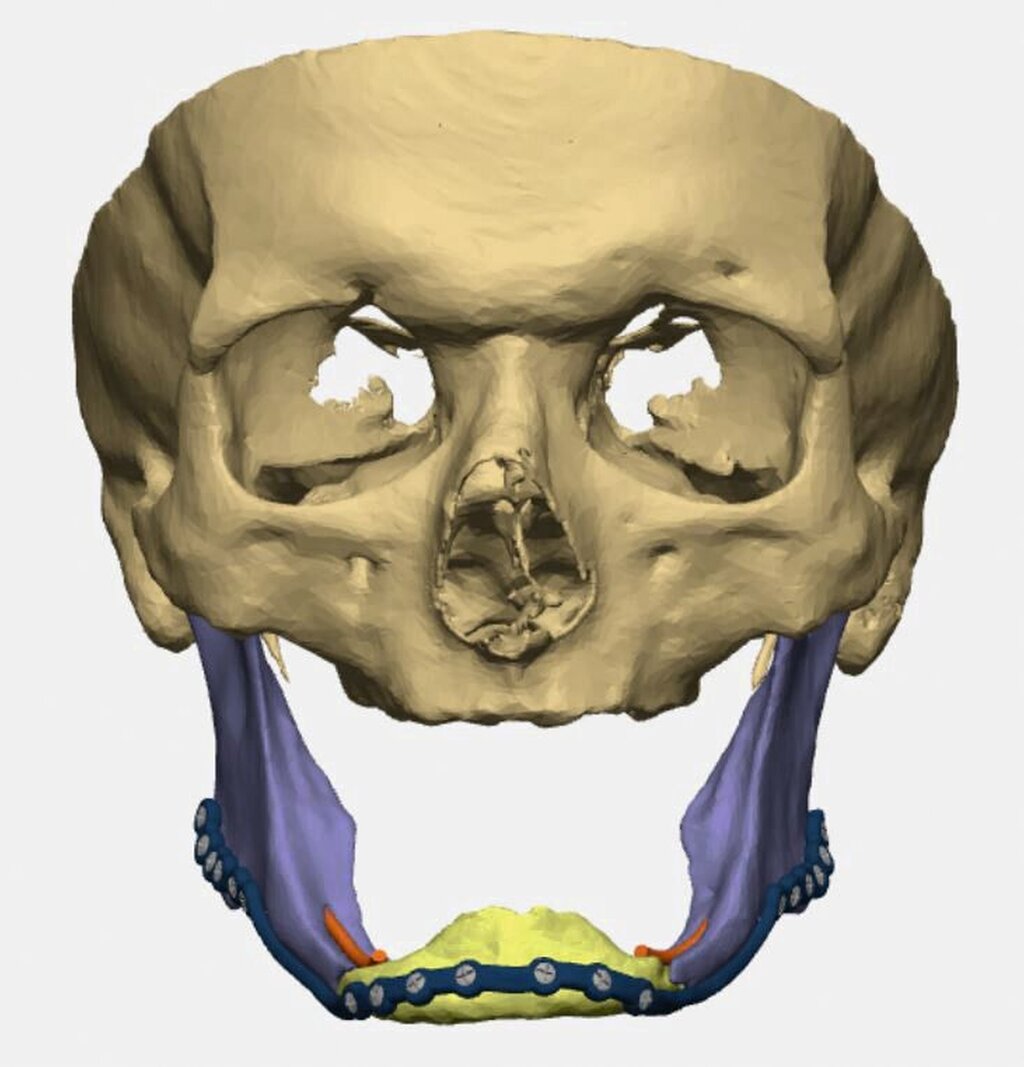

Bei zahnlosem Ober- und Unterkiefer erfolgte die virtuelle Repositionierung des frakturierten Unterkiefers (Abbildung 2a). Mittels CAD/CAM-Verfahren wurde eine stabile Rekonstruktionsplatte aus Titan (patientenspezifisches Implantat; PSI) geplant und hergestellt. Dabei sollte die Position des PSIs im Bereich des Unterkieferkorpus weit kaudal an der Basis sein, so dass später bei der Anpassung einer neuen Unterkieferprothese keine Interferenzen auftreten (Abbildung 2b).

Gleichzeitig konnte durch eine optimierte Bohrlochposition der Nervus alveolaris inferior geschont werden, eine Neurolyse brauchte nicht geplant zu werden. Außerdem wurden an die Zielreposition angepasste Bohrschablonen (drilling guides) hergestellt, die ein Vorbohren der späteren Schraubenlöcher in der exakten Zielposition ermöglichen (Abbildung 2c). In Kombination mit dem PSI sollte so eine Auto-Reposition des Unterkiefers durch die vorgegebenen Bohrlöcher erfolgen.

Operativ verwendeten wir einen beidseitigen extraoralen Zugang. Intraoperativ ließen sich die drilling guides exakt einbringen und wurden durch Schrauben fixiert. Nach Bohrung der vorgegebenen Bohrlöcher und Anbringen des PSIs konnte die Fraktur anatomisch reponiert und stabilisiert werden. Der postoperative Verlauf gestaltete sich komplikationslos, so dass der Patient am vierten postoperativen Tag nach Hause entlassen werden konnte. Vier Wochen nach der Operation zeigte sich in der klinischen Kontrolle ein reizfreier Situs mit guter Wundheilung.